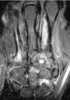

Bone grafting is a surgical procedure that replaces missing bone in order to repair bone fractures that are extremely complex, pose a significant health risk to the patient, or fail to heal properly. Some small or acute fractures can be cured without bone grafting, but the risk is greater for large fractures like compound fractures. [Source: Wikipedia ]